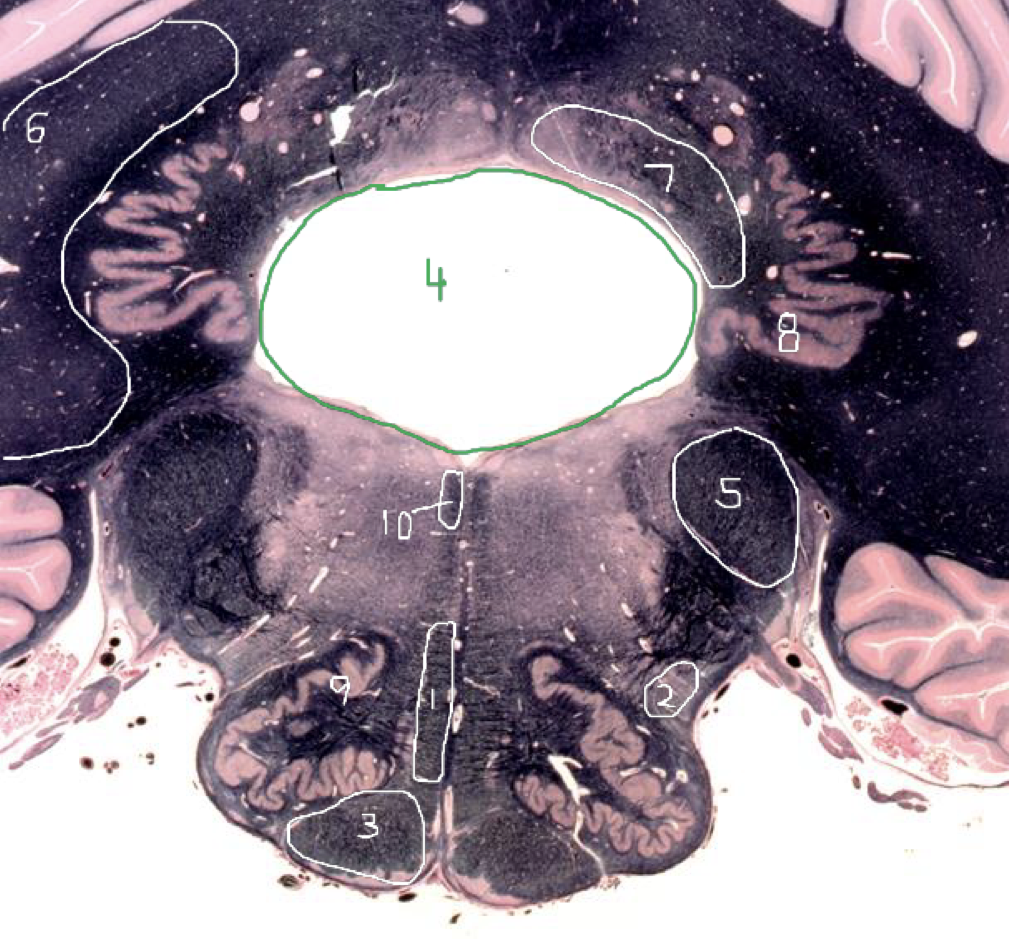

4

4th Ventricle - Caudal Pons

5

Inferior Cerebellar Peduncle - Caudal Pons

6

Middle Cerebellar Peduncle - Caudal Pons

7

Superior Cerebellar Peduncle - Caudal Pons

8

Dentate Nuclei (Cerebellum) - Caudal Pons

9

Inferior Olivary Nucleus - Caudal Pons

10

Medial Longitudinal Fasciculus (MLF) - Caudal Pons